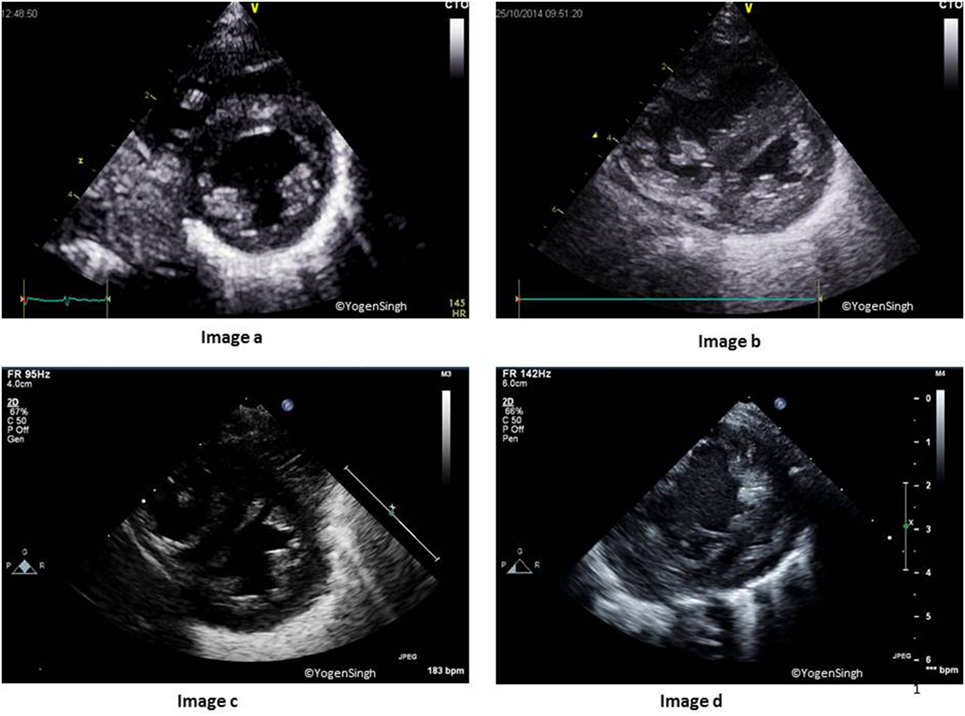

This is best assessed by using PSAX sweep views. Normally, LV is seen as a circular structure in PSAX view because LV pressure is much higher than the RV pressure. In presence of pulmonary hypertension, there may be flattening of IVS, making LV a D-shaped structure. The severity of flattening or reversal of IVS reflects severity of pulmonary hypertension as shown in Figure 7 (38, 42).

Figure 7. Interventricular septum (IVS) and left ventricle (LV) shapes in pulmonary hypertension. Image a shows normal IVS and LV shape with LV being a circular-shaped structure on sweep PSAX view. Images b–d show change in shapes with increasing flattening of IVS in presence of mild, moderate, and severe pulmonary hypertension, respectively.